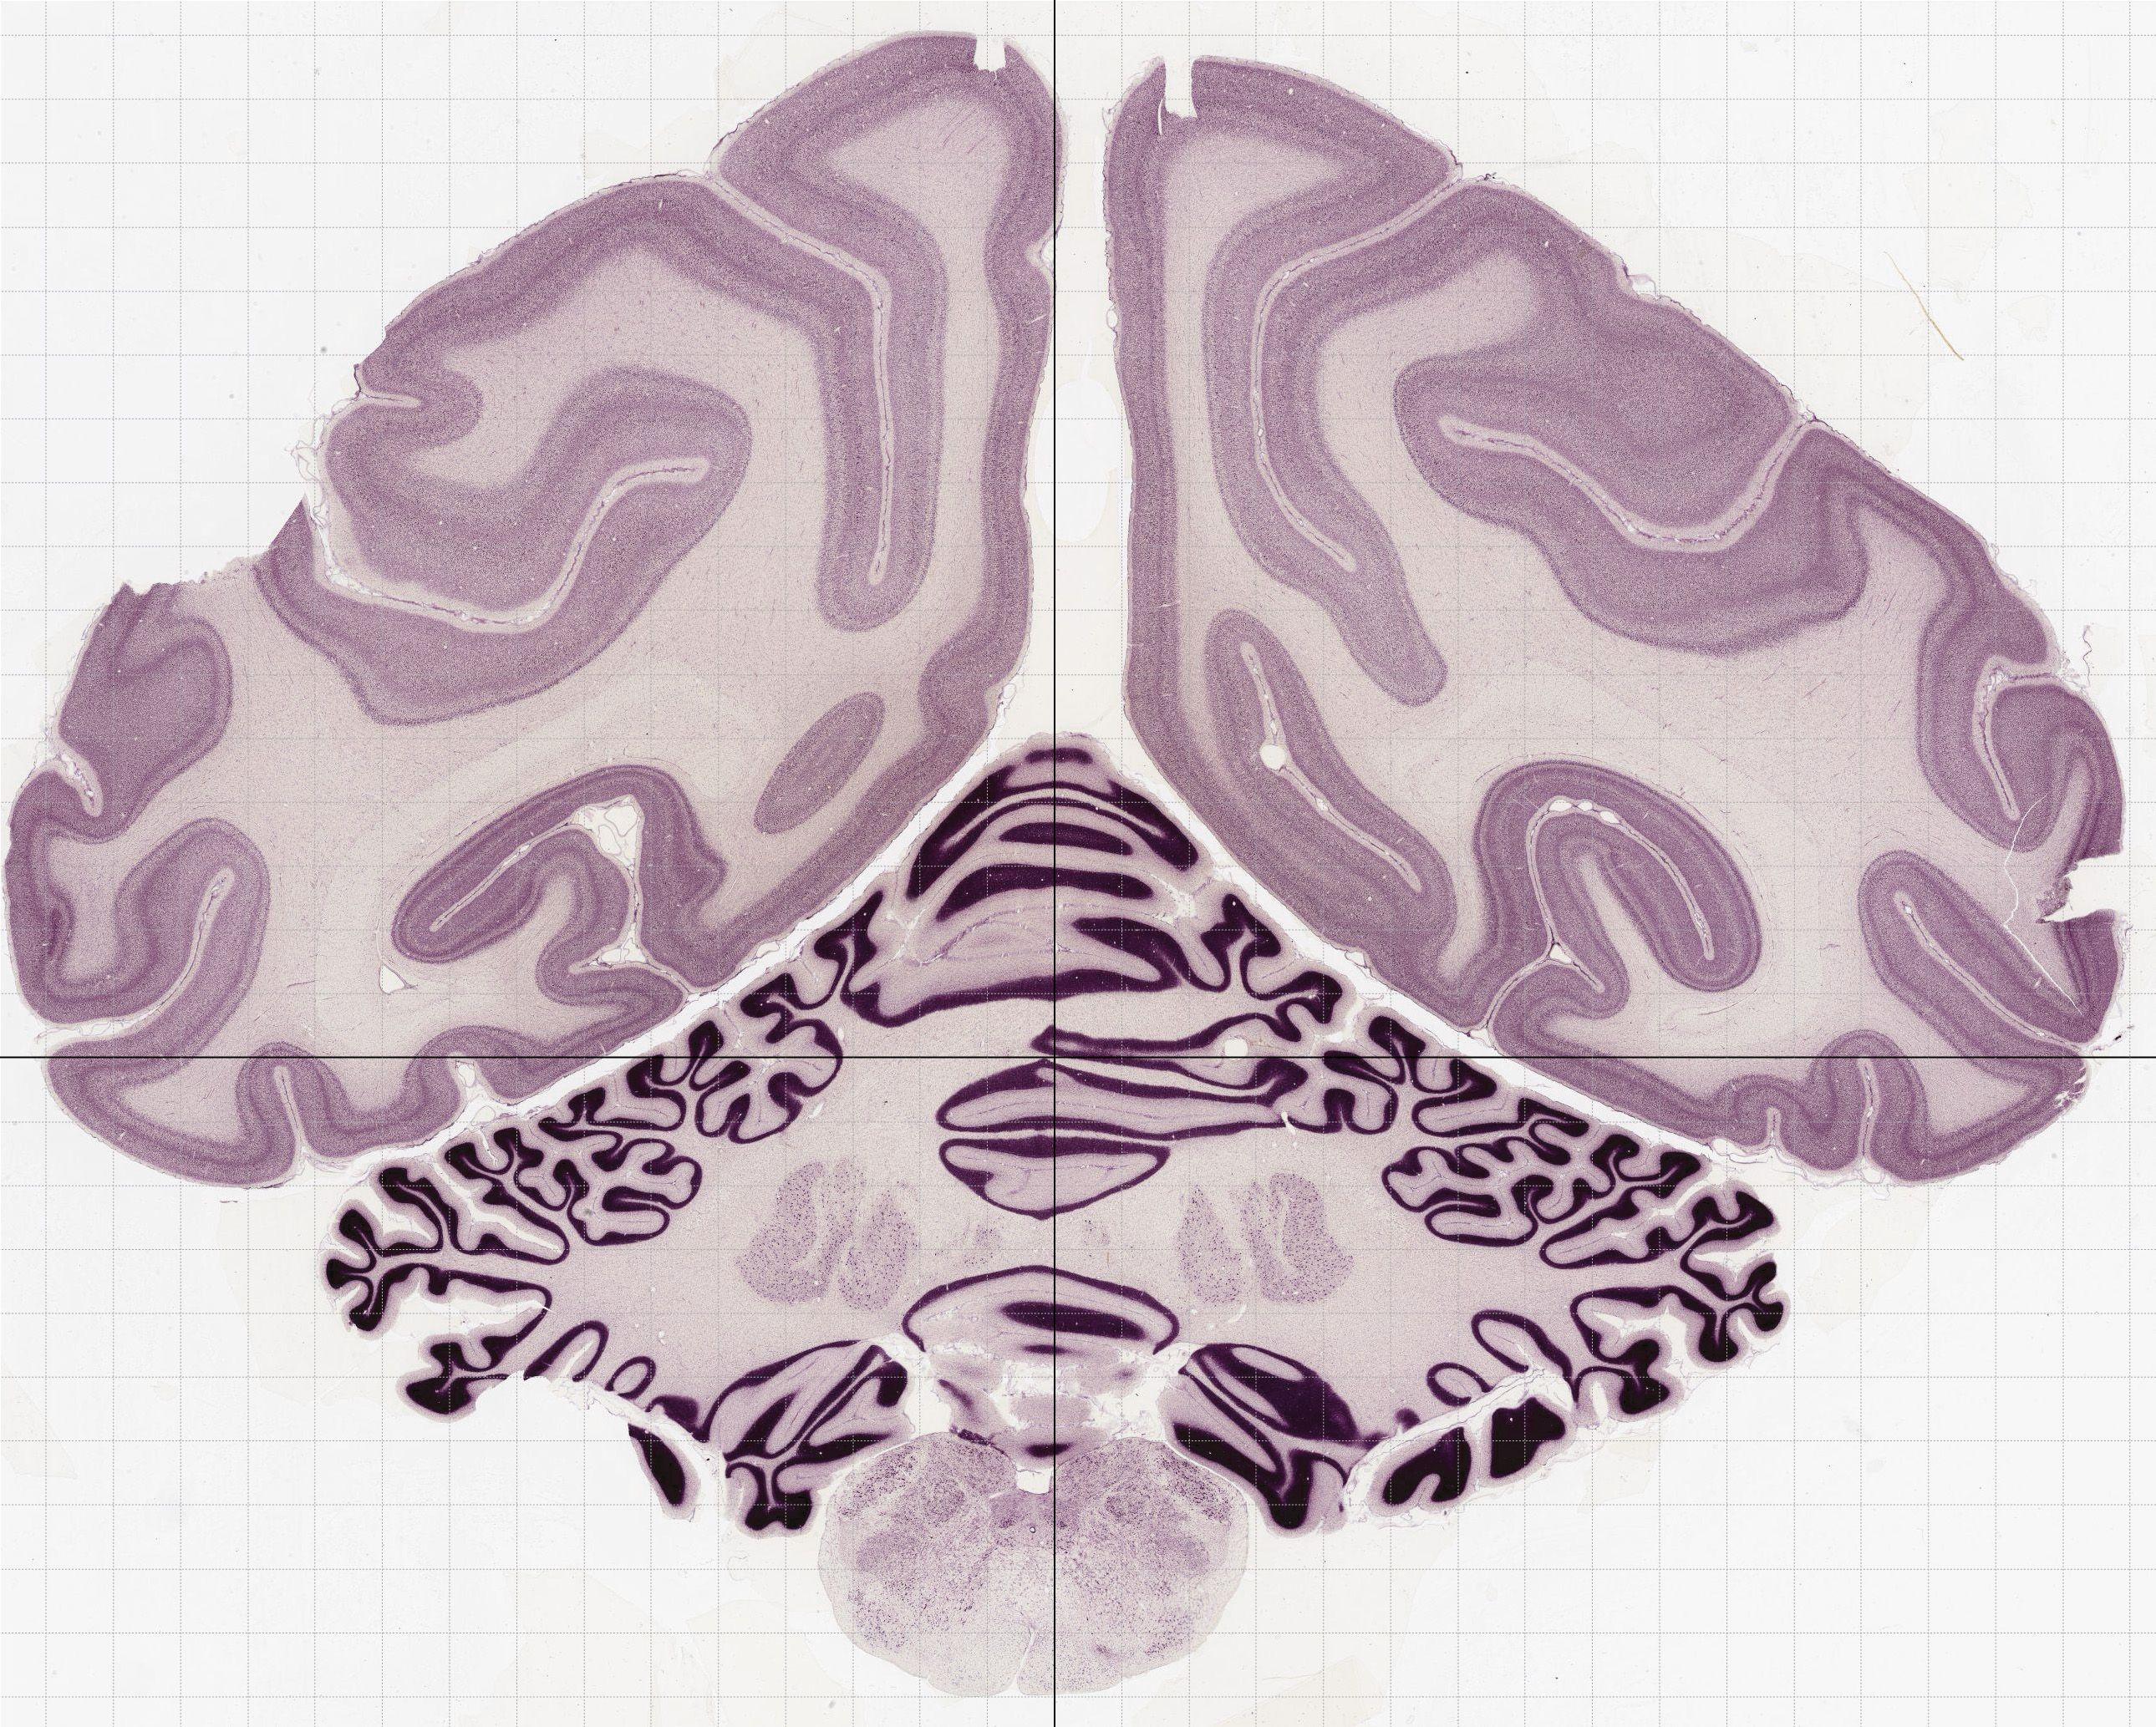

Datasets -> Macaca Mulatta -> Nissl, coronal, histo, Whole-Brain, adult

[ Metadata ]   ·   Source: Edward G. Jones

thumbnail

0565 - labeled